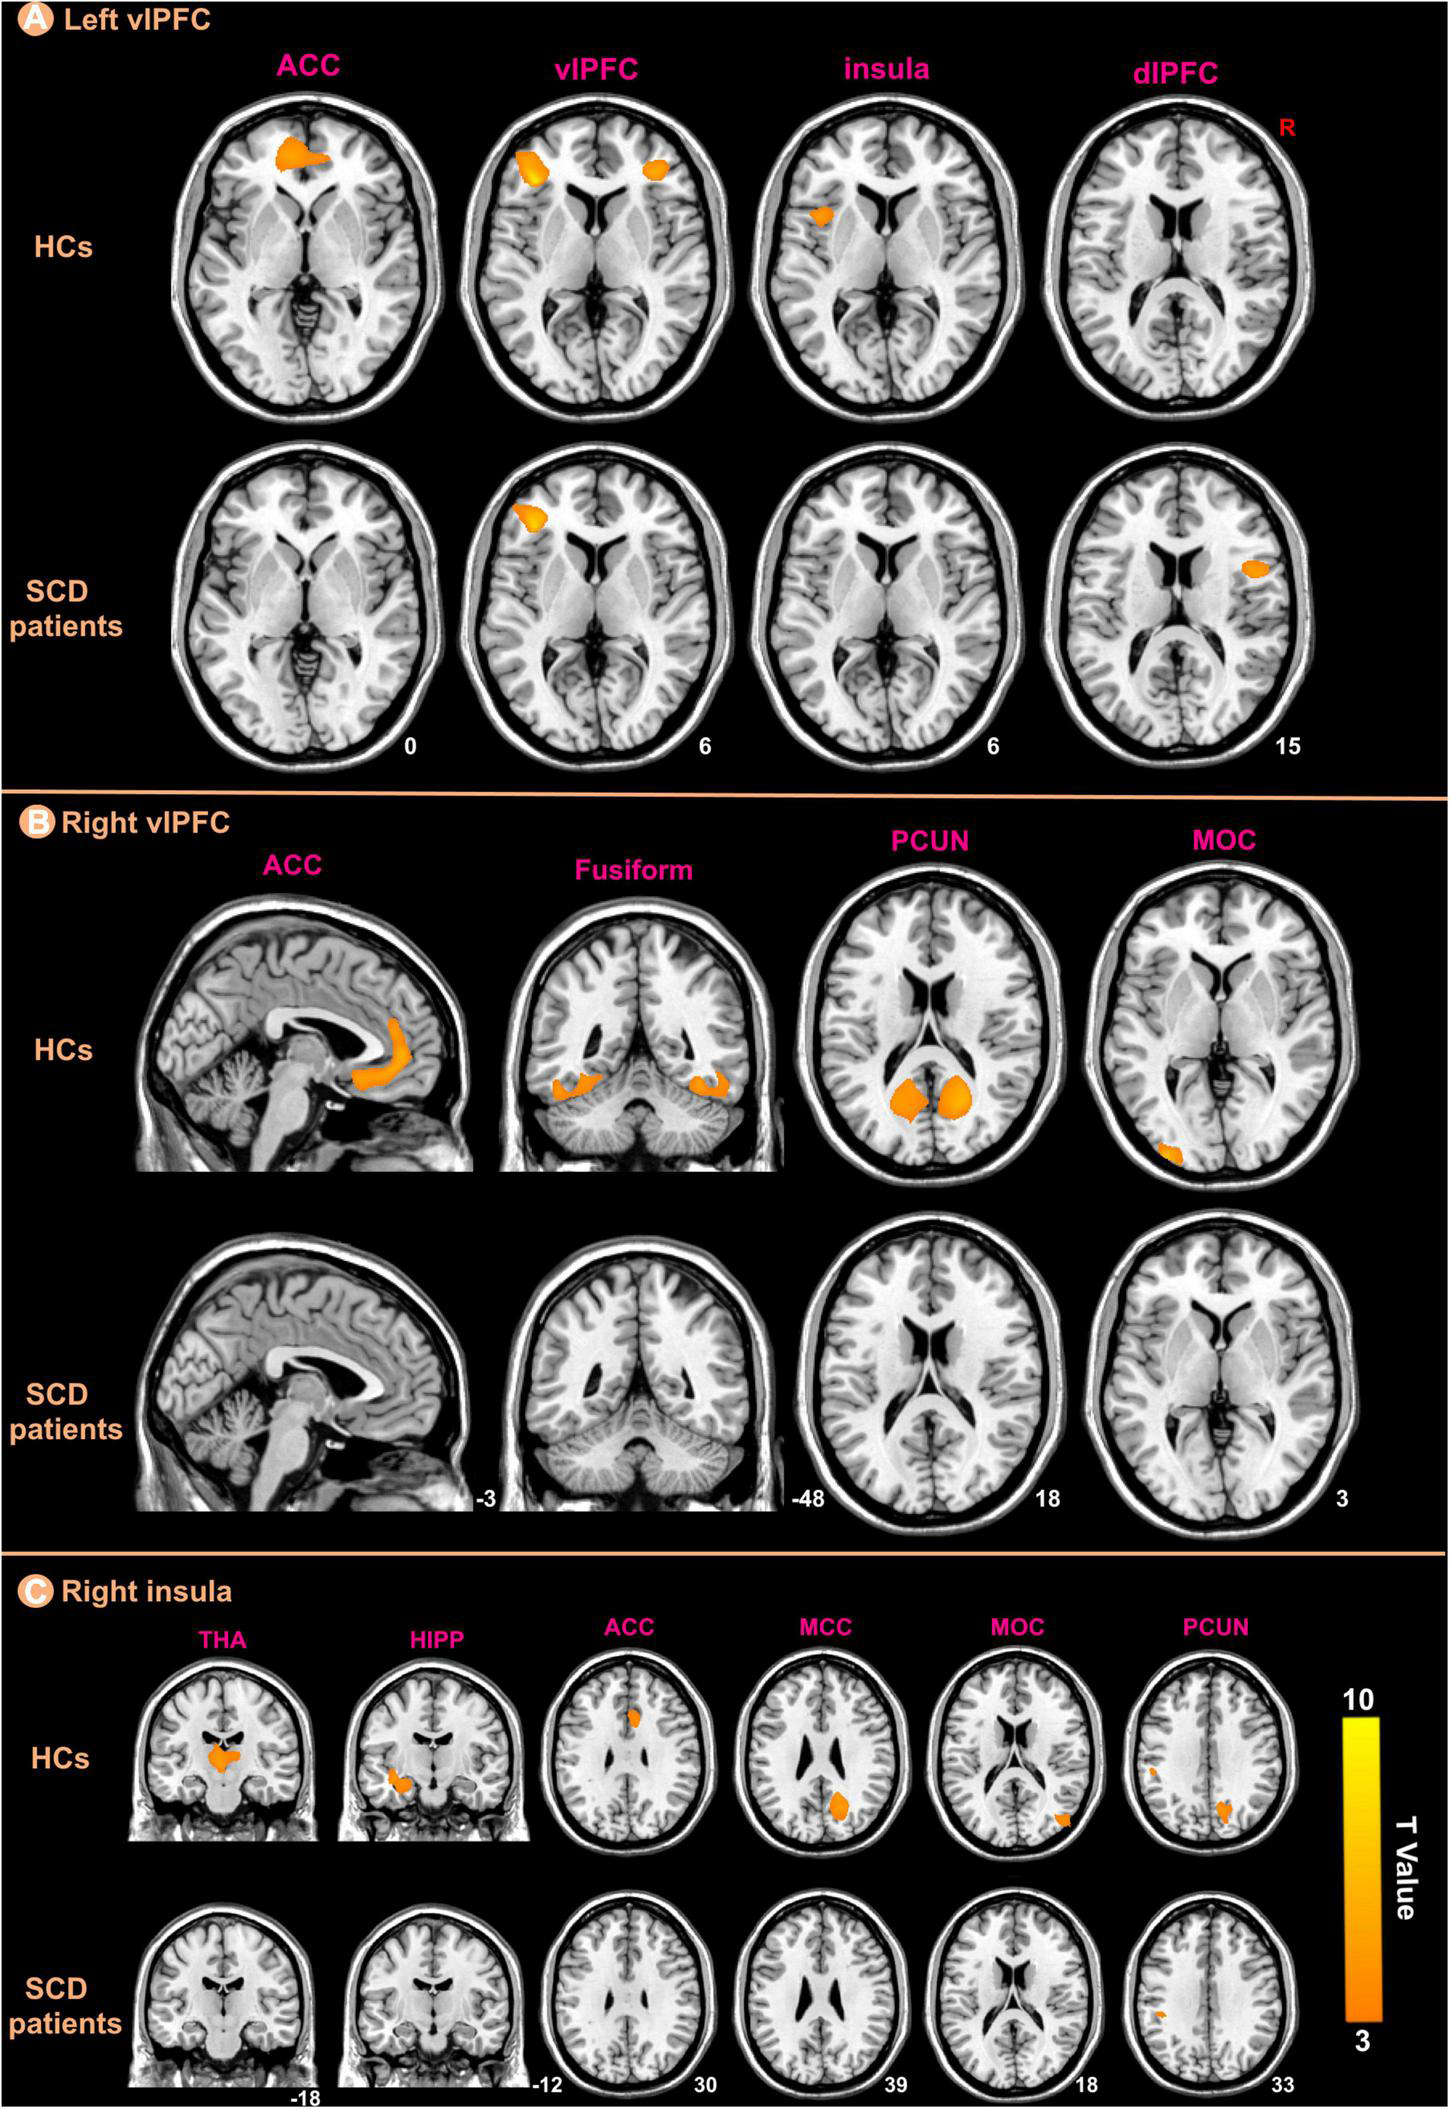

Structural covariance results

We selected three regions including bilateral vlPFC and right insula from those that showed significant differences between the groups in the GMV analysis as ROIs for structural covariance analysis. Figure 5 indicated the different patterns of structural covariance in the two groups associated with the three ROIs and we focused only on the positive correlation. There was an abnormal structural association between the left vlPFC and regions, including the left anterior cingulate cortex (ACC), right vlPFC, left insula, and right dorsolateral prefrontal cortex (dlPFC) in the patients with SCD compared to the HCs. The left ACC, left middle occipital cortex (MOC), bilateral fusiform and bilateral precuneus (PCUN) showed decreased structural covariance with the right vlPFC in patients with SCD compared to HCs. For the right insula ROI, decreased structural covariance was observed between the right insula and regions including the right median cingulate cortex (MCC), right PCUN, right MOC, left HIPP, left THA, and right ACC.

FIGURE 5

The ROIs-based structural covariance patterns in subjective cognitive decline (SCD) patients and healthy controls (HCs). The structural covariance patterns related with the left vlPFC (A), the right vlPFC (B), and the right insula (C) ROIs in the two groups.

In this study, we investigated altered PerAF, GMV, and structural covariance patterns in patients with SCD, and the main findings are described below. (1) Patients with SCD had higher PerAF primarily in the right HIPP and right THA; (2) patients with SCD showed significantly decreased GMV in the bilateral vlPFC and right insula; (3) For the left vlPFC ROI, patients with SCD showed decreased structural association with the left ACC, right vlPFC, left insula and right dlPFC. For the right vlPFC ROI, patients with SCD showed decreased structural association with the left ACC, left MOC, bilateral fusiform, and bilateral PCUN. For the right insula ROI, decreased structural covariance was observed between the right insula and regions including right MCC, right PCUN, right MOC, left HIPP, left THA, and right ACC; (4) We performed a between-group analysis of structural covariance patterns by calculating the slope differences. Results indicated that structural covariance differences of the ROIs were still found to be significantly related to the left ACC, left MOC, left fusiform and bilateral PCUN. (5) There were negative correlations between the MMSE and PerAF in the right HIPP, right ITC, and left THA in patients with SCD; (6) There were positive correlations between the MMSE and GMV in the bilateral vlPFC, left STC, and right insula in patients with SCD.